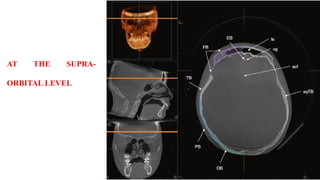

AT THE SUPRA-

ORBITAL LEVEL

Images in the axial orthogonal plane demonstrate a continuum of anatomy

extending from the supraorbital region of the frontal bone to the hyoid bone